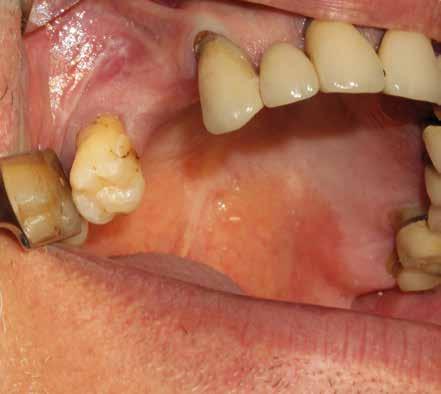

Alla visita di rivalutazione è emerso un ulteriore peggioramento della situazione, confermata anche dall’esame radiografico, con parodontopatia, sanguinamento al sondaggio, infiammazione diffusa, alitosi, difetto parodontale verticale mesiale a 2.3, residui radicolari 1.4, 1.6, 1.7, 3.6, 3.8 e carie destruenti di 1.5, 2.6, 3.5, 3.7 (con lesione endoperio) e 4.7 con estrusione e carie (Figg. 1, 2)

Si è consigliato di procedere per gradi, con bonifica di tutti gli elementi malati e irrecuperabili e successivamente sostituire gli elementi mancanti o con protesi rimovibili o con una protesi fissa sostenuta da impianti (Fig. 3).

La proposta che il paziente ha accettato è stata poi quella, previa bonifica di tutti gli elementi irrecuperabili, di riabilitare con impianti prima il 1° e 4° quadrante e in seguito il 2° e 3° e procedere poi alla protesi definitiva in un’unica soluzione.

riferico. Si è eseguito la maggior parte delle estrazioni in un’unica seduta operatoria, a esclusione degli elementi 2.6 e 4.7 che sono stati mantenuti perché presentavano mobilità ma non segni di focolai infettivi attivi e che si è deciso di estrarre in un secondo momento. Il follow-up post estrattivo ha consentito anche di valutare la risposta tissutale e la guarigione degli alveoli. Non è stata sospesa la terapia con l’acido acetilsalicilico. Il PRGF è stato importante per evitare alveoliti che avrebbero rallentato la guarigione (Figg. 4-6).

Dopo tre mesi dalla prima fase estrattiva sono stati ripetuti gli esami ematochimici dai quali l’emoglobina glicata del paziente è scesa a 7.2%. Abbiamo pertanto avviato con lo studio pre-implantare che prevede la ceratura diagnostica e gli esami radiologici più avanzati per scegliere i giusti impianti e la loro sede corretta.

L’esame CBCT ha rivelato un quantitativo di osseo sufficiente a procedere con l’intervento implantare, anche se erano ancora visibili le zone delle estrazioni; inoltre ha evidenziato una lesione osteolitica a carico del 3.5 che abbiamo dunque deciso di estrarre (Figg. 7-20).